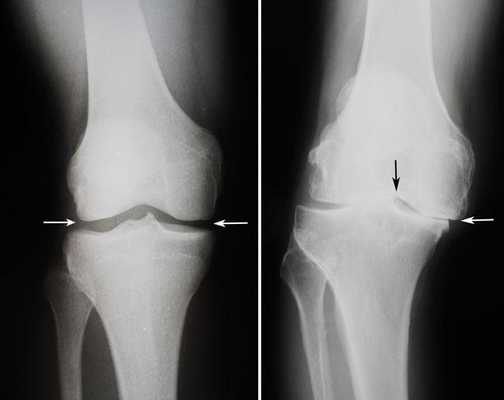

Динамика болезни на рентгене.

Артроз коленного сустава на рентгене.

Показания к замене

Посмотрите на рентген, на нем вы видите, до какой степени при запущенном гонартрозе изношен гиалиновый хрящ, обеспечивающий гладкое скольжение суставных поверхностей. Концевые участки костей грубо деформируются нарушая функции сгибания и разгибания конечности вызывая интенсивный болевой синдром.